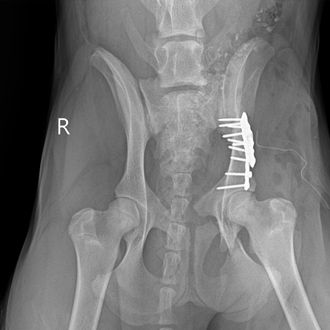

외상 응급

(교통사고)

출혈, 장기 손상, 골절 등 복합 손상이 동반될 수 있습니다.

전신 상태 평가 후 단계적인 치료 계획이 필요합니다.